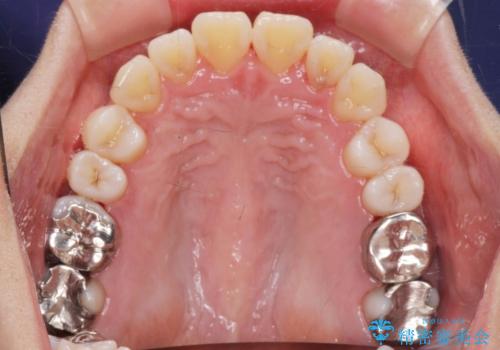

捻れた奥歯 突き出た前歯を治したい

- 出っ歯に見える前歯、捻れてしまった小臼歯の改善を求めて来院されました。

マウスピースでは改善の難しい小臼歯のねじれをまず部分ワイヤー矯正で改善し、その後マウスピース矯正で前歯の突出感を改善します。

時間はかかりましたが、捻れ、かみ合わせ、前歯の角度の改善が達成され満足いただくことができました。